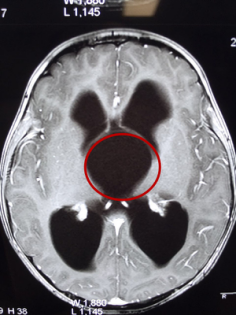

突破!上海蓝十字脑科医院开展脑室镜蛛网膜囊